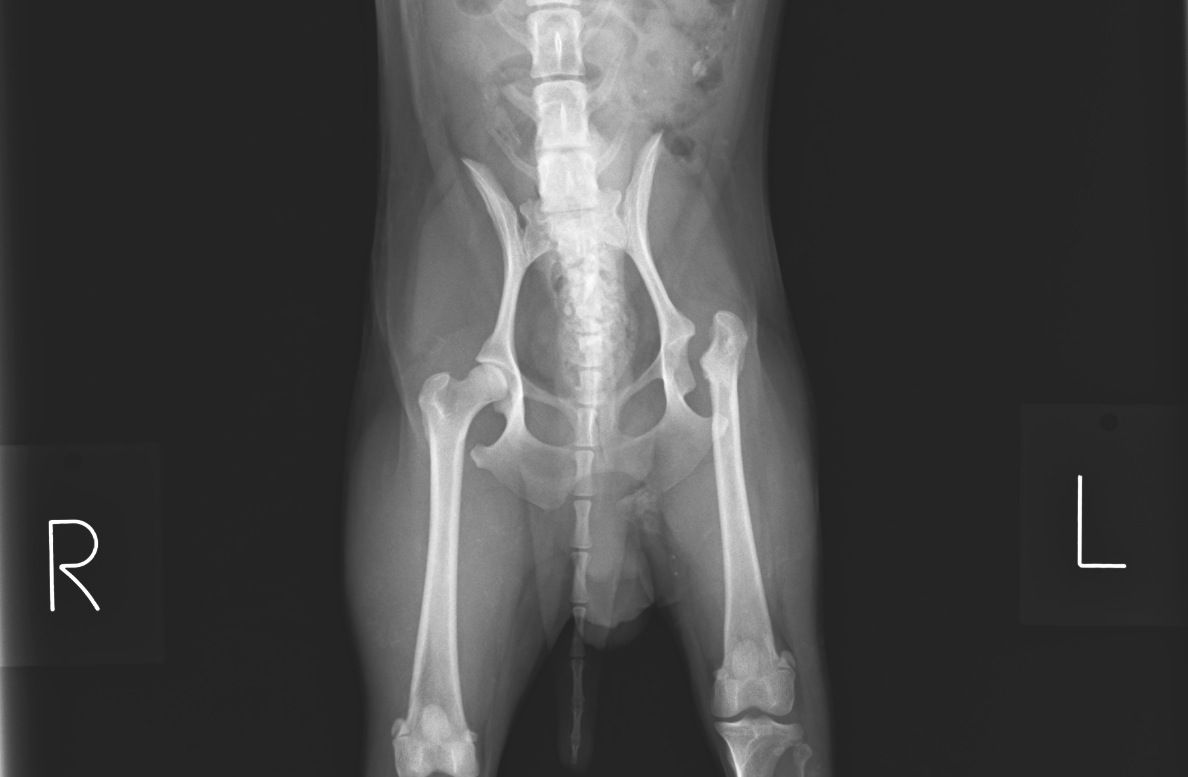

レッグ・カルベ・ぺルテス

本日の症例は、以前レッグ・カルベ・ぺルテス病と診断されて、

外科的手術を受けたわんちゃんです。

レッグ・カルベ・ぺルテス病は若いわんちゃんに起こりやすく、

大腿骨の骨頭が壊死してしまう病気です。

今回のわんちゃんは術後の経過観察のため来院されました。

レントゲン画像では左の大腿骨が股関節から離れていますが、術後はこの状態が正常で、

現在普通に歩けるようになっています。